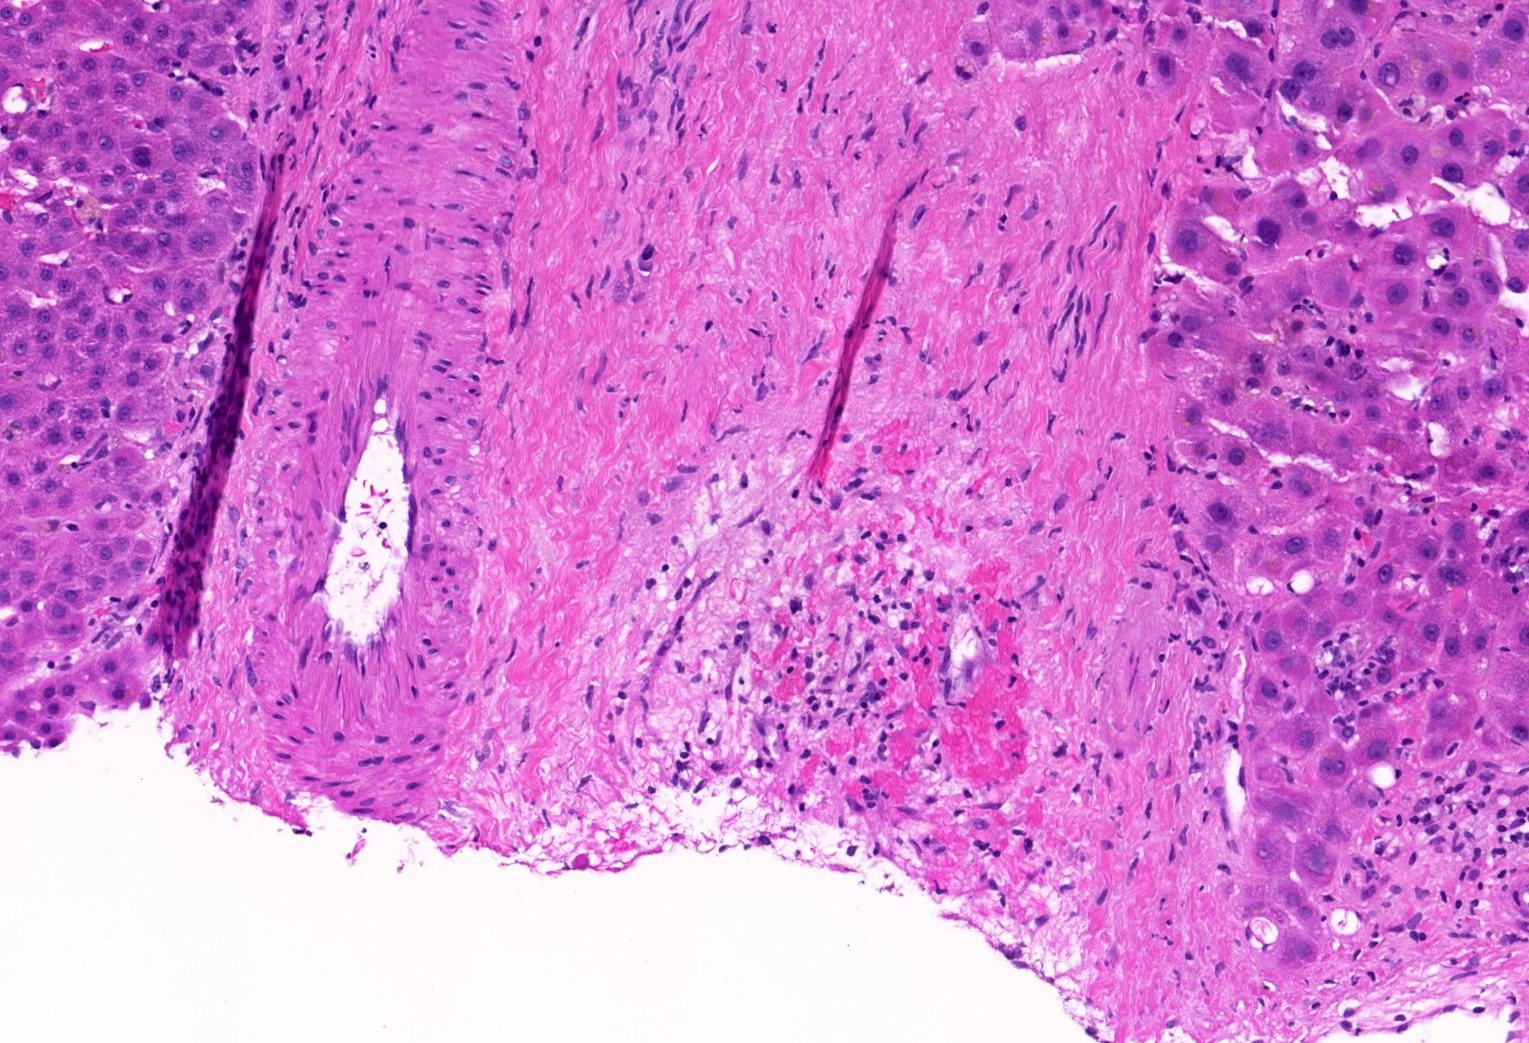

- Vascular changes (Pediatr Transplant 2018; 22:e13124, Am J Transplant 2018;18:1534):

- Obliterative portal venopathy with nodular regenerative hyperplasia-like changes

- Distinct fibrosis patterns (Am J Transplant 2016;16:603, Transplantation 2017;101:2062, Clin Transplant 2018;32:e13227, Liver Transpl 2016;22:1593, Liver Transpl 2018;24:897):

- Dense acellular portal collagen deposition: portal collagenization

- Distinct subsinusoidal and perivenular fibrosis